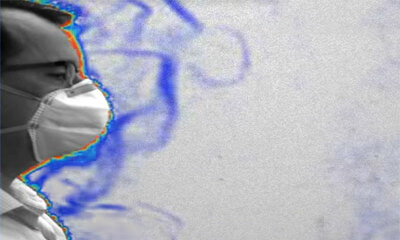

Voilà pourquoi les masques faciaux réduisent le risque d’infection

La principale façon de transmettre du Covid-19 de personne à personne est par le biais d'aérosols ou des petites gouttelettes créées par la respiration, les éternuements ou la toux. La portée de l'air expiré peut être ef...